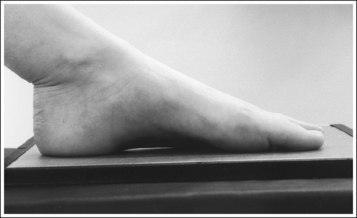

• Determining required obliquity. To determine whether a 30- or 60-degree rotation is needed, view the medial aspect of the patient's foot in an AP projection to judge the height of the patient's longitudinal arch. Less obliquity is required in a patient with a low longitudinal arch than in a patient with a high arch. If the patient has a low arch (Figure 6-20; also see Figure 6-15), rotate the patient's foot approximately 30 degrees medially; if the patient's foot has an average arch (Figure 6-21; also see Figure 6-16), rotate the foot approximately 45 degrees medially; and, if the patient's arch is high (Figure 6-22; also see Figure 6-17), rotate the foot approximately 60 degrees. The average arch requires 45 degrees of rotation. As the foot is rotated, keep the lower leg, ankle, and foot aligned to judge the degree of foot obliquity better.

The height of the longitudinal arch can be determined by measuring the amount of cuboid demonstrated posterior to the navicular bone. The average lateral foot projection demonstrates approximately 0.5 inch (1.25 cm) of the cuboid, as shown in Figure 6-23. Because the bones that form the foot arch are held in position by ligaments and tendons, weakening of these tissues may result in a decreased or low arch. On a lateral foot projection, this decrease in arch height is demonstrated as a decrease in the amount of cuboid demonstrated posterior to the navicular bone. Figure 6-20 shows a lateral foot projection of a patient with a low longitudinal arch and approximately 0.25 inch (0.6 cm) of cuboid posterior to the navicular bone, whereas Figure 6-22 shows a patient with a high arch and approximately 0.75 inch (2 cm) of cuboid posterior to the navicular bone.